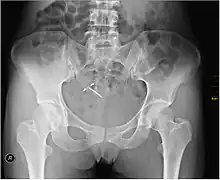

Regardless of IUD type, there are some potential side effects that are similar for all IUDs. Some of these side effects include bleeding pattern changes, expulsion, and pelvic inflammatory disease (especially in the first 21 days after insertion). The occurrence of IUD migration is rare, with reported rates in medical literature varying between 0.1% and 0.9%. However, when migration occurs, it can lead to serious complications such as uterine perforation and, in rare cases, bladder perforation. Bladder perforation, while uncommon (affecting only 2% of displaced IUDs), can result in symptoms like urinary frequency, hematuria, and stone formation, often necessitating surgical intervention for removal[54]. Regular monitoring and imaging, such as ultrasound or CT scans, are recommended to detect such complications early and ensure timely treatment. A small probability of pregnancy remains after IUD insertion, and when it occurs, there is a greater risk of ectopic pregnancy.[55]